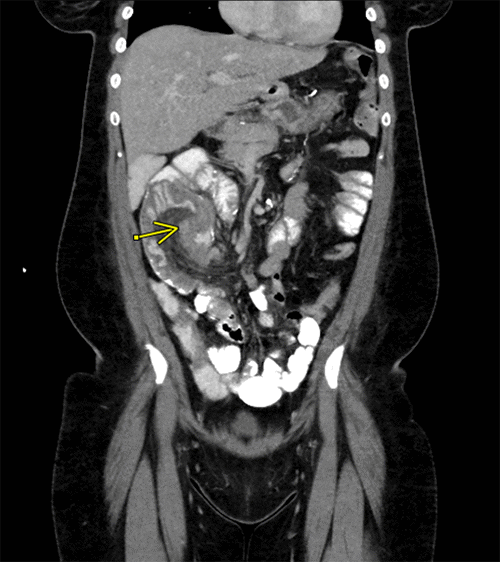

Figure 1. CT Scan Demonstrating Intussusception. Published with Permission

Nine years post-RYGB, the patient presented to the ED once again with complaints of intermittent abdominal pain for one week. Notably, she did not report experiencing nausea, obstipation, or abdominal distention. Upon presentation, her BMI was 32.5, and her vital signs were stable. During the abdominal examination, periumbilical tenderness was noted. Laboratory tests revealed a white blood cell count (WBC) of 7300/mcl; electrolyte levels were within the normal range. A CT scan (Figures 2 and 3) showed a small bowel intussusception involving the ileum, spanning approximately 20 cm, with signs of partial obstruction. Subsequently, the patient underwent a diagnostic laparoscopy, which revealed retrograde intussusception of the common channel at the anastomosis. Fortunately, the intussusceptum was easily reducible, and there were no indications of necrosis or edema. No bowel resection or enteropexy was deemed necessary. Following the procedure, the patient experienced an uneventful postoperative recovery, and she was discharged on POD 1.

Figure 2. Coronal CT Image Demonstrating Intussusception at Second Presentation. Published with Permission